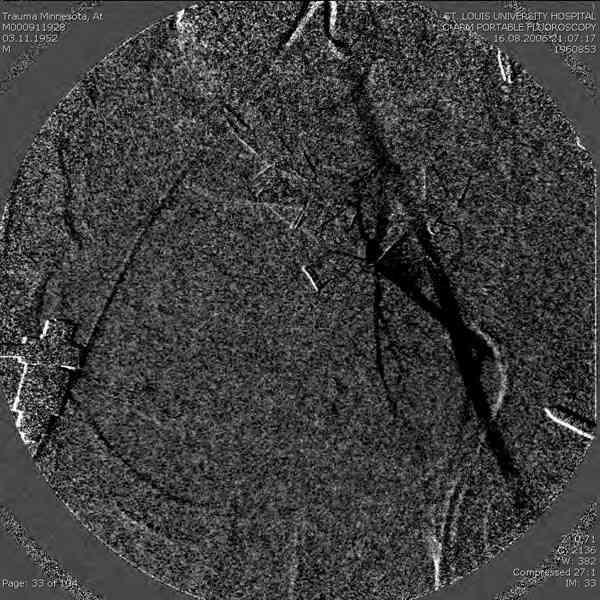

Примерно такой фиксатор наложил вчера ночью, но патология была экстренная травма: больному 53 года, поступил после мотоциклетной травмы, черепно-мозговой, абдоминальной, челюстно лицевой с потерей одного глаза, сосудистой и из скелета перелом крестца слева с диастазом симфиза и множественные переломы ребер.

Здесь соблюдался алгоритм больному с внутритазовым кроветечением после нестабильного перелома таза.

Шоковым с повреждением таза, перед КТ исследованем накладывается антишоковые трусы.

Для стабилизации перелома и кровопотери, сперва была попытка наложения простыни вокруг таза для уменшения объема таза. Для оперативного доступа в области живота и передней части таза простыню заменили на Beam Bag (матрац который после удалении воздуха принимает контуры тела).

Одновременно с хирургами, которые занялись ксплоративной лапаротомией, мы приступили к фиксации временным аппаратом для уменьшения диастаза симфиза. После установки аппарата удалось стабилизировать давление, потом наше место занял сосудистый хирург, который нашел кровоточащую левую артерию epigastrica. Кровоточаший сосуд затромбизировал эндоваскулярно введением 4 coil placement.